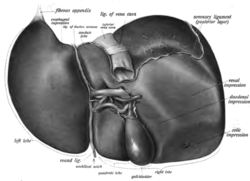

Gross anatomy

Gross anatomy traditionally divided the liver into two portions– a right and a left lobe, as viewed from the front (diaphragmatic) surface; but the underside (the visceral surface) shows it to be divided into four lobes and includes the caudate and quadrate lobes.[12]

The falciform ligament, visible on the front of the liver, divides the liver into a left and a much larger right lobe. From the visceral surface, the two additional lobes are located between the right and left lobes, one in front of the other. A line can be imagined running from the left of the vena cava and all the way forward to divide the liver and gallbladder into two halves.[13] This line is called Cantlie's line.[14]

Other anatomical landmarks exist, such as the ligamentum venosum and the round ligament of the liver (ligamentum teres), which further divide the left side of the liver in two sections. An important anatomical landmark, the porta hepatis, also known as the transverse fissure of the liver, divides this left portion into four segments, which can be numbered starting at the caudate lobe as I in an anticlockwise manner. From this visceral view, seven segments can be seen, because the eighth segment is only visible in the parietal view.[15]

Surfaces

On the diaphragmatic surface, apart from a large triangular bare area where it connects to the diaphragm, the liver is covered by a thin double-layered membrane, the peritoneum, that help reduces friction against other organs.[16] This surface covers the convex shape of the two lobes where it accommodates the shape of the diaphragm. The peritoneum folds back on itself to form the falciform ligament and the right and left triangular ligaments.[17]

The visceral surface or inferior surface, is uneven and concave. It is covered in peritoneum apart from where it attaches the gallbladder and the porta hepatis.[16]

Impressions

There are several impressions on the surface of the liver which accommodate the various adjacent structures and organs. Underneath the right lobe and to the right of the gallbladder fossa, are two impressions, one behind the other and separated by a ridge. The one in front is a shallow colic impression, formed by the hepatic flexure and the one behind is a deeper renal impression accommodating part of the right kidney and part of the suprarenal gland.[18]

The suprarenal impression is a small triangular depressed area on the liver. It is located close to the right of the fossa between the bare area and the caudate lobe and immediately above the renal impression. The greater part of the suprarenal impression is devoid of peritoneum and it lodges the right suprarenal gland.[19]

Medial to the renal impression is a third and slightly marked impression, lying between it and the neck of the gall-bladder. This is caused by the descending portion of the duodenum, and is known as the duodenal impression.[19]

The inferior surface of the left lobe of the liver presents behind and to the left the gastric impression.[19] This is moulded over the upper front surface of the stomach, and to the right of this is a rounded eminence, the tuber omentale, which fits into the concavity of the lesser curvature of the stomach and lies in front of the anterior layer of the lesser omentum.